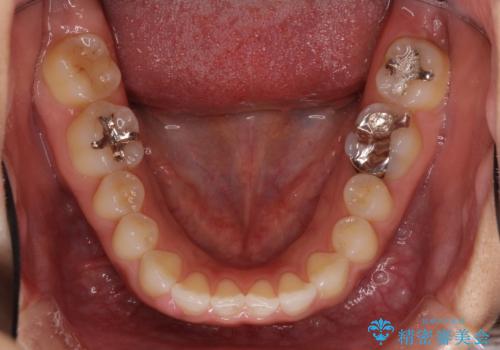

- 前歯の隙間を気にして来院された患者様です。

隙間、捻転ともに軽微でありましたが、下顎前歯の突き上げにより隙間ができていたため、インビザラインを用いて咬み合わせを改善しながら前歯の歯列を整えていくこととしました。